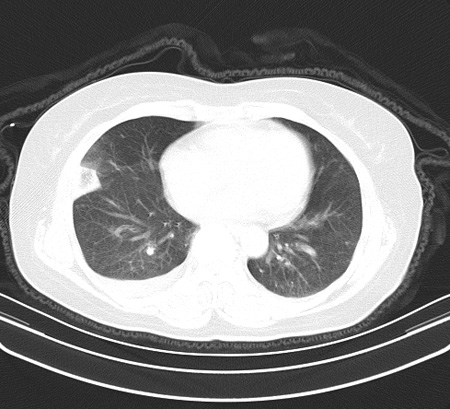

以下是引用余辉在2009-2-19 20:10:00的发言:[br]多考虑急性感染性病变,右中叶尚可见多枚小斑片状影,多为化脓性肺炎,双侧胸腔积液

以下是引用随光逐影在2009-2-19 20:33:00的发言:[br]1)考虑右肺炎症;建议抗炎治疗后复查。2)双侧胸腔积液(以右侧为甚)。

以下是引用花凤凰在2009-2-19 20:46:00的发言:[br]病人有发热,胸痛急性起病,主要病变位于右肺中叶外侧段,呈楔行改变,位于外带胸膜下,考虑为肺梗塞可能!!!!!!!!!!!!!!!!!!!!!!!!!!!!!!!!!!!